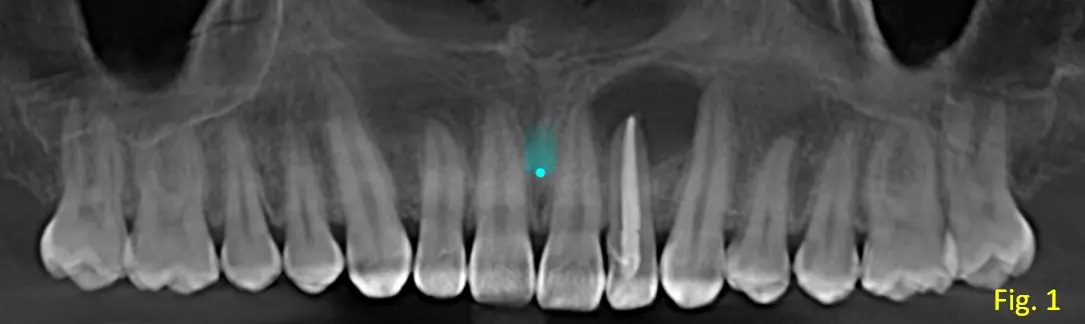

En la región anterior del maxilar superior, específicamente en la zona periapical de la pieza 22 (incisivo lateral superior izquierdo), se observa lesión hipodensa de bordes definidos, forma ovalada, sin compromiso de la raíz (ver fig. 1, vista panorámica).